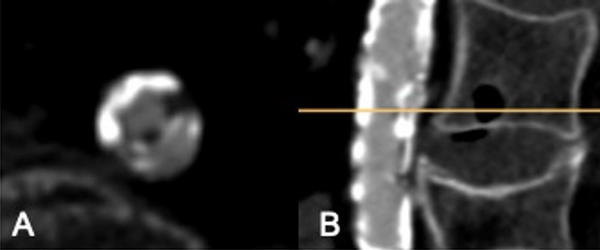

Actually, two different expandable sheaths are commercially available. The Edwards eSheath is available in two sizes (14 or 16 F), and the Boston iSleeve® in one size (14 F). The Edwards eSheath® is softer and more flexible compared to the Boston iSleeve®, which can be an advantage in severe kinking without severe circular calcification. In contrast, the stiffer shaft of the Boston iSleeve® may be favorable in more calcified anatomies, which need to be smoothly dilated (Figure 2, Videos 4 and 5).

Figure 2: CT-scan with severe circular calcified abdominal stenosis (diameter 5x3mm) (A: axial B: sagittal)